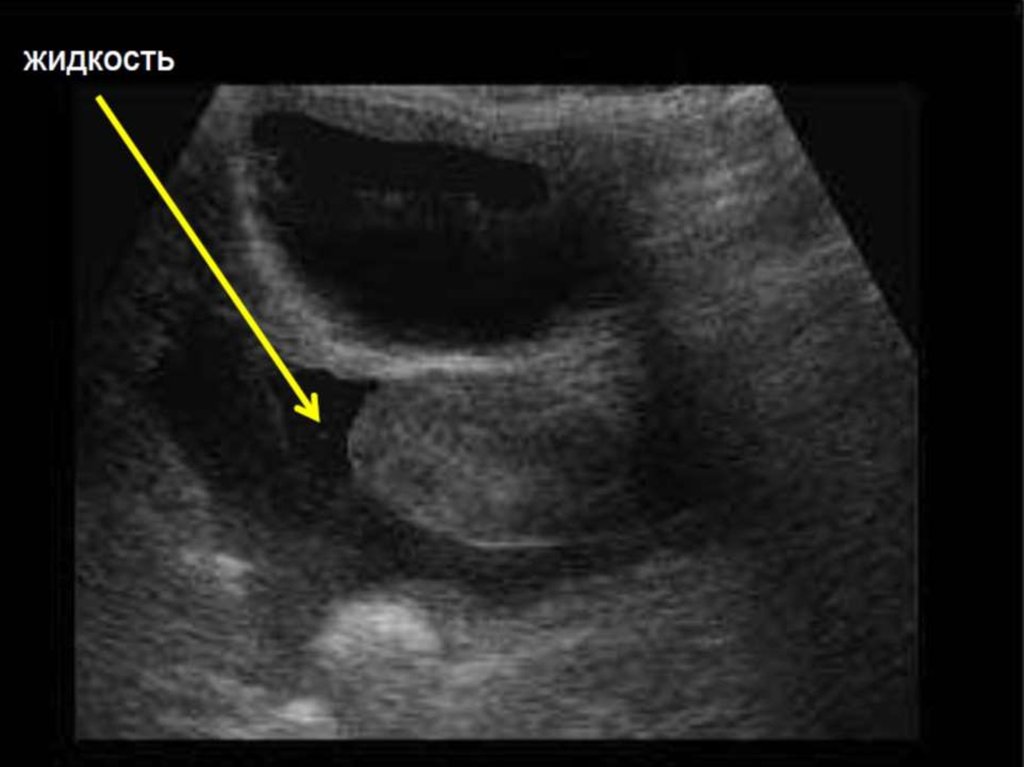

Гемоперитонеум